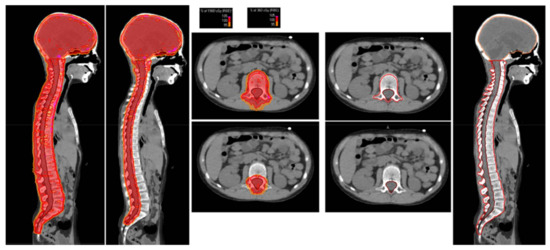

2.3. Radiation Treatment Planning

3.3. Proton Therapy